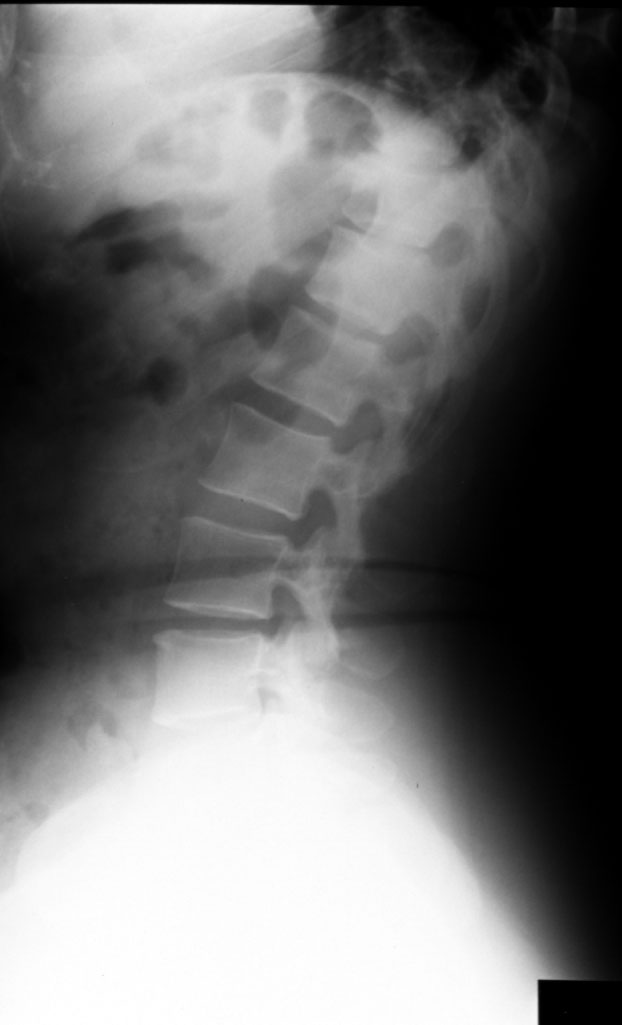

Normal Lumbar Spine (L lateral) Identify: Vertebral body, pedicle, lamina,

spinous process, intervertebral disc